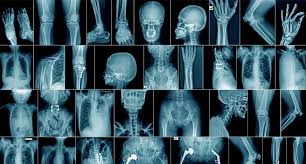

Radiology department

Radiology Service is one of Medical and Allied Health Sciences (MAHS) services and designed for executing general radiography and ultra sound exams and send back results.